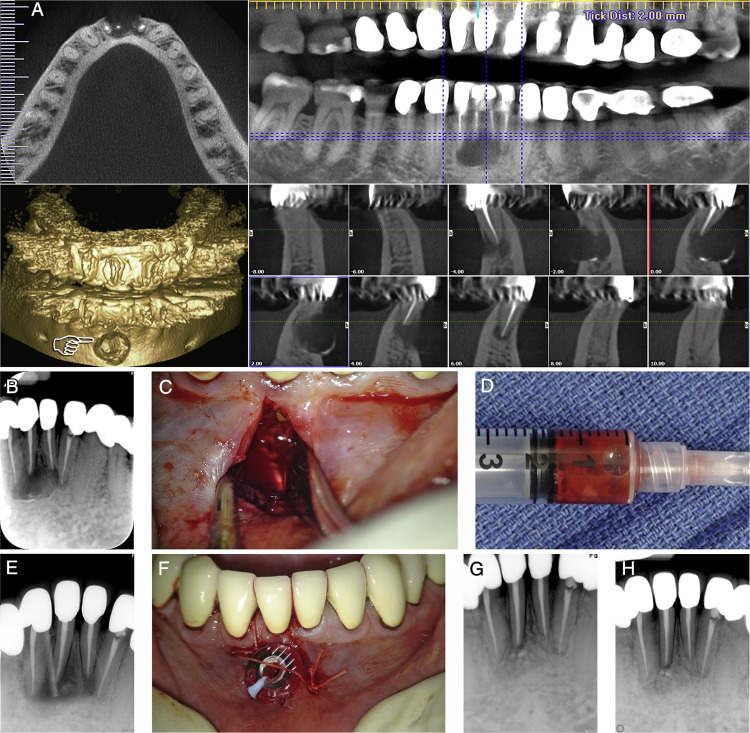

Hình ảnh nang chân răng

– Đường rạch có thể hình vợt, hình thang hoặc ngách lợi. Bóc tách vạt niêm mạc màng xương bằng cây bóc tách (Hình 12).

– Dùng curet bóc tách nang. Dùng curet cỡ lớn nhất có thể để tránh làm

thủng vỏ nang.

– Cắt cuống răng đến sát đáy nang bằng mũi khoan, sau khi đã hàn kín ống tủy.

– Kiểm tra kỹ ổ xương, làm nhẵn bờ xương, bơm rửa bằng nước muối sinh lý.

– Đặt lại vạt niêm mạc màng xương và khâu phục hồi bằng chỉ nilon.

Gây tê tại chỗ

Mở vạt bộ lộ nang, bóc tách nang

Bơm rửa kỹ bằng dung dịch nước muối sinh lý pha với betadine sau khi bóc tách loại bỏ hết nang, tổ chức viêm

Hỗn hợp ghép gồm collagen, xương ghép, PRF

Tiến hành ghép vật liệu

Khâu đóng vạt